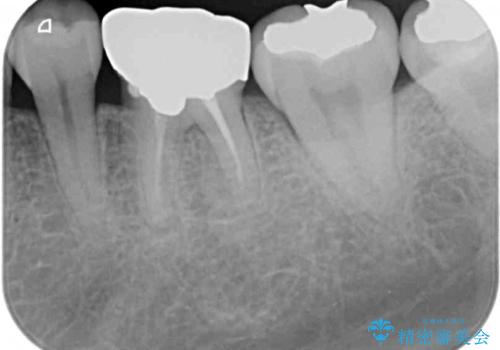

- 口を開けたときに目立ってしまう銀歯をセラミックに替えたいとのことで来院された患者様です。

上顎や親知らずにも銀歯がありましたが、今回の治療では目立つ下顎の銀歯4歯をセラミッククラウンやセラミックインレーに置き換えることにしました。